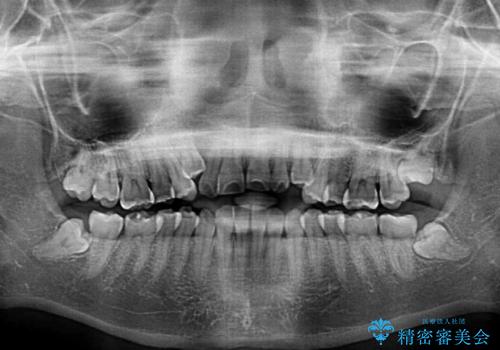

- 前歯のデコボコや八重歯、舌癖による開咬を気にして来院された患者様です。

目立たない装置を希望されたので、上顎が裏側装置のハーフリンガルを選択し、上顎小臼歯1本を抜歯して、補助装置を併用して矯正治療を行うこととしました。

補助装置を事前に使用したことで、あっという間に八重歯が改善し、ハーフリンガルにしては1年半もかからずに治療を終えることができました。